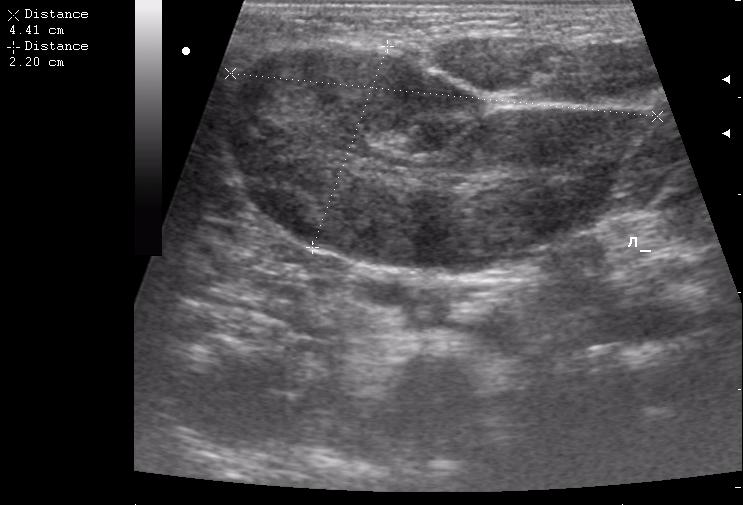

левая околоушная железа

левая поднижнечелюстная железа

правая околоушная железа

расширенный выводной проток

Да уж,явное увеличение околоушных желез.Да и реакция л.узлов значительная.Интресно понаблюдать в динамике.Слишком большие подчелюстные узлы.Спасибо за случай.